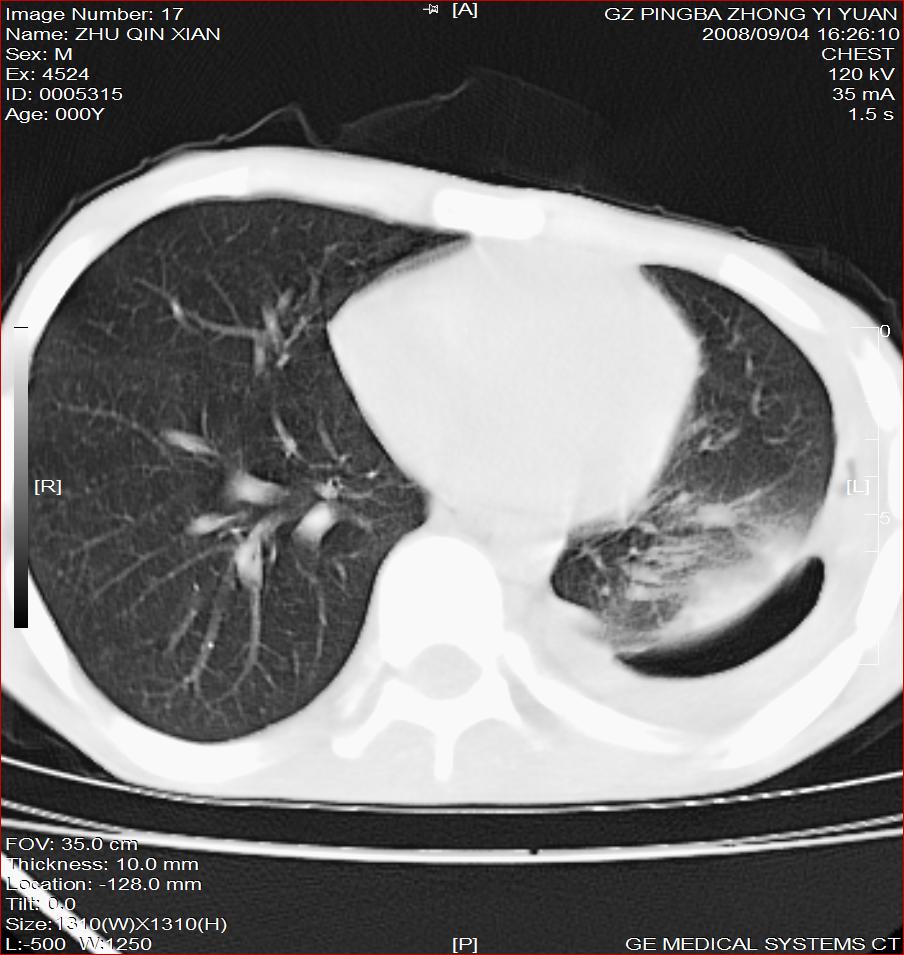

以下是引用随光逐影在2008-9-4 20:05:00的发言:[br]1)考虑两肺结核。2)左侧胸膜炎(胸膜肥厚、粘连,胸腔积液)。3)左侧局限性气胸。

以下是引用子十在2008-9-4 19:34:00的发言:[br]左上肺结核并空洞及双肺播散。节段性肺不张、胸腔积液、胸膜肥厚粘连。[br]